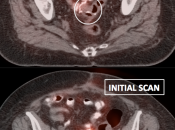

Assessing Response to Therapy:

- Early Response: Non-responders can be offered alternative therapy.

- Late Response: Assess success or failure of therapy, and ultimate outcome.

Recurrence & Restaging: (Most common indication)

- Distinguishing recurrence from post-therapeutic inflammation/scarring.